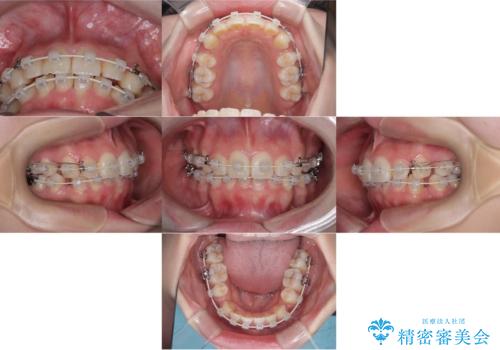

- 「歯のでこぼこと捻じれを治したい」を主訴に来院された患者様です。矯正検査の結果、上顎前歯がかなり唇側傾斜という結果になったので上下左右4番を抜歯をしワイヤー矯正で治療を行いました。

抜歯矯正でしたが順調に治療が進み2年で矯正治療を終えることが出来ました。歯のでこぼこや捻じれが治り、口元も下がって患者さんも大変満足されていました。